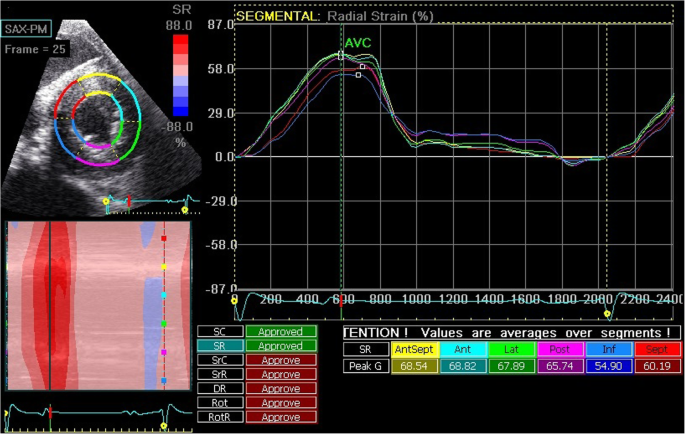

Off-line analysis was performed using dedicated software (EchoPAC Software Version 11.2, GE Healthcare, Diegem, Belgium). For each image, 3 cardiac cycles were analyzed and then averaged. End-diastole was defined as the peak R wave on the ECG. To evaluate the longitudinal LV wall deformation, the right parasternal four-chamber long axis images were analyzed and the region of interest (ROI) was set by tracing the LV endocardial border from the septal insertion of the mitral valve until the insertion point on the lateral myocardial wall. The width of the ROI was set to cover the myocardial wall but not the epicardium (Fig. 1) and was automatically divided by the software into 6 segments: basal (basSept), mid (midSept) and apical (apSept) part of the interventricular septum, and basal (basLat), mid (midLat) and apical (apLat) part of the LV free wall (LVFW). Data generated from the apical segments were not included in the segmental analysis but for the global measurements, those segments were included by the software. Therefore, global values are not reported in this study. To evaluate LV radial and circumferential wall deformation, short axis images (caudal right on screen) were analyzed. The ROI was set by tracing the endocardial border and adapting the width of the ROI. The software divided the ROI automatically in 6 segments based on the human heart orientation. In horses, AntSept and Sept represent the interventricular septum, Inf and Post represent the cranial LVFW and Lat and Ant define the caudal LVFW (Fig. 2).

Right parasternal short axis image of the left ventricle, taken at end-systole. The region of interest is automatically divided into six segments (Sept and AntSept for the interventricular septum; Ant and Lat for the caudal left ventricular free wall; Inf and Post for the cranial left ventricular free wall). The segmental traces for radial strain are displayed

Tracking quality of all images was calculated by the software and verified visually by the operator. When necessary, ROI was adapted manually until tracking quality was good [10, 11]. For the longitudinal motion, strain (SL), strain rate (SrL) and displacement (DL) curves were displayed. From the short axis images, curves for radial strain (SR) and strain rate (SrR) and for circumferential strain (SC) and strain rate (SrC) were derived. The timing of aortic valve closure (AVC) was automatically calculated by the software algorithm based on the segmental curves. Strain values were reported by the software as systolic peak values occurring before AVC and the absolute maximal peak value which could also occur after the calculated AVC. From the strain and displacement curves maximal segmental strain or displacement was measured and average strain over all segments was calculated manually. From the strain rate curves, segmental systolic (S), early diastolic (E) and late diastolic (A) peak values were measured and average strain rate over all segments was calculated [10, 11].